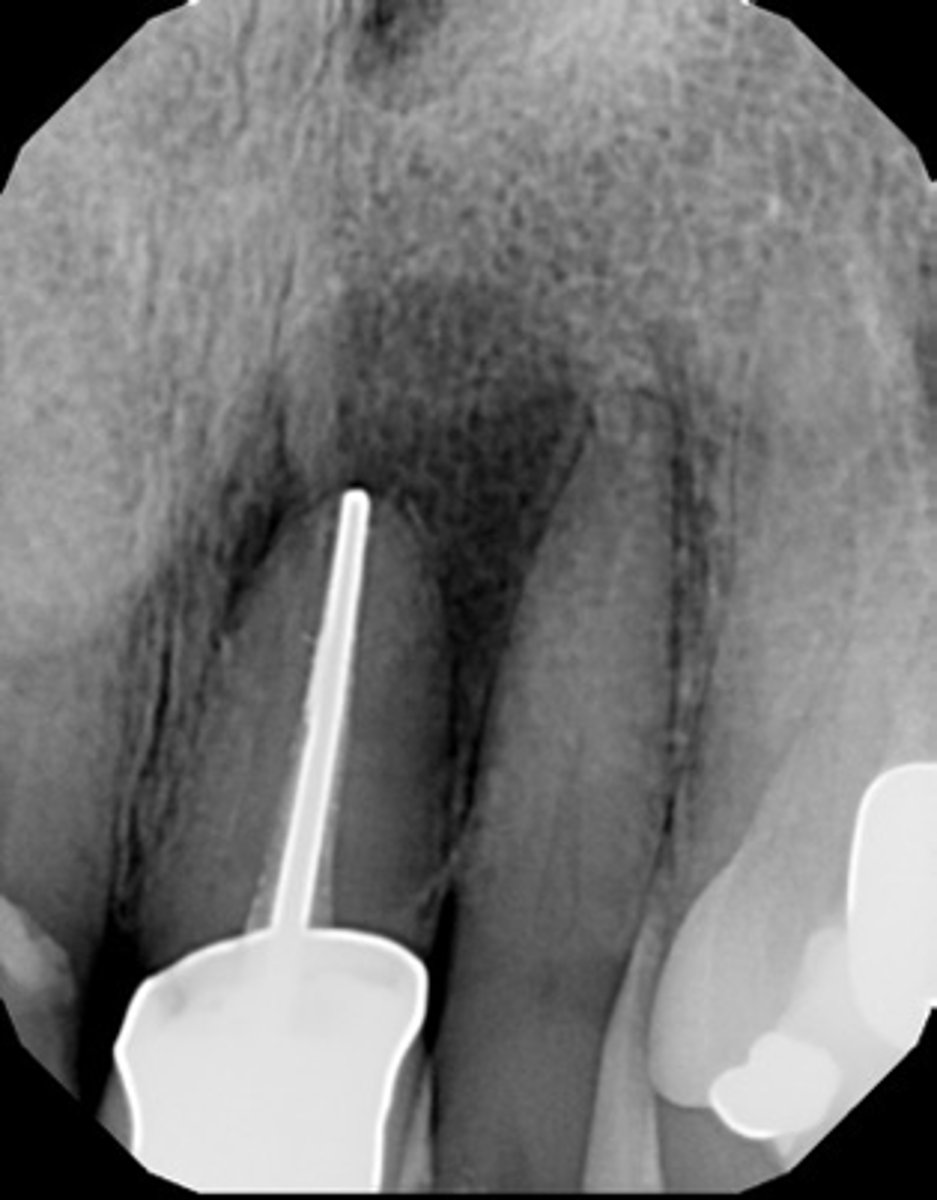

perforation

ID the procedural error: